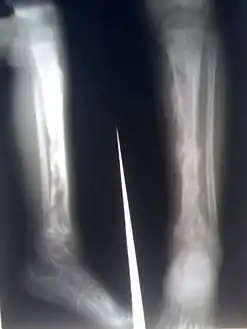

يحدث هذا الخمج بشكل أكبر في العظامالطويلة أو أجسام الفقرات إن هذا النوع من ذات العظم والنقي شائع بشكل خاص عند طرفي العمر : الأطفال وكبار السن كما إنه شائع عند مدمني المخدرات الوريدية والمضعفين مناعيا يتظاهر المرضى عادة ببدء حاد للألم مضض وحمى وقد يوجد تورم نسج رخوة فوق العظم المصاب . في الأسبوعين الأولين من الإصابة يمكن أن تكون الصور الشعاعية سلبية أو تظهر تورم نسج رخوة فقط . مخبريا ترتفع سرعة التثفل ويرتفع تعداد الكريات البيض أيضا . تكون زروع الدم إيجابية عند نصف الحالات فقط . يجب أن يجرى للمرضى خزعة بالإبرة وزرع العظم المصاب مالم تكن نتائج زرع الدم معروفة قبل ذلك . ويجب أن تستمر المعالجة بالصادات المناسبة من 4 - 6 أسابيع